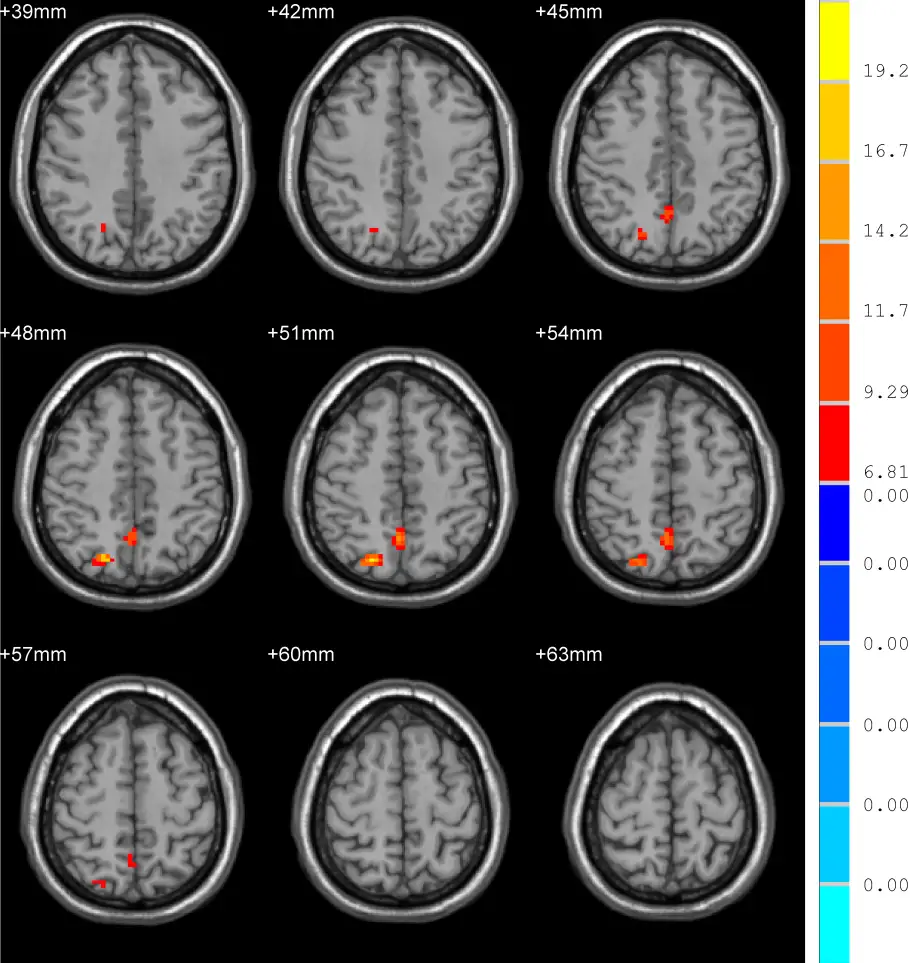

Comparing with the healthy controls, TLE patients showed significantly increased NH values in the right superior parietal lobule (SPL) as well as right precuneus (PCU). In addition, reaction time (RT) was found significantly longer in TLE patients in comparison with healthy controls. Last but not the least, there were no significant relationship between the clinical variables and abnormal NH values in TLE patients.

Our results indicated that abnormal NH of DAN was in the TLE patients

and stressed the crucial role of DAN in the pathophysiology of

cognitive damage in TLE. We also found that executive function (EF)

significantly weakened in the TLE patients.